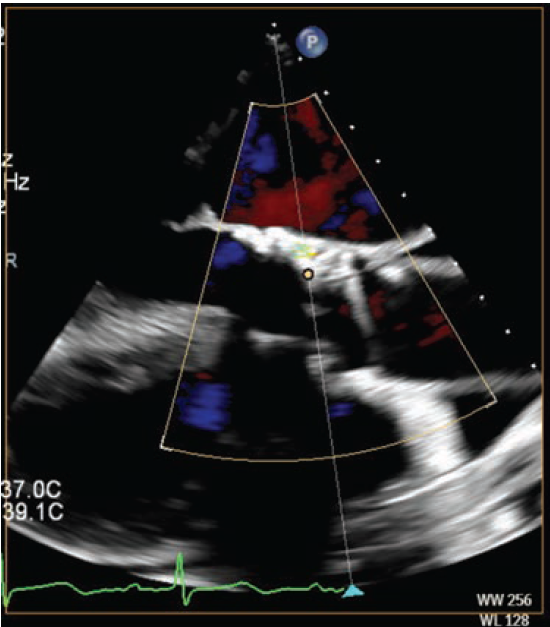

At the one-month follow-up appointment, she reported recurrence of shortness of breath with activity. A repeat echocardiogram showed moderate to severe PVL, and her ejection fraction had improved to 40%-45%, with an aortic valve gradient of 9 mmHg. We elected to perform PVL closure. Intraoperative transesophageal echocardiography (TEE) revealed moderate to severe PVL, with two jets on either side of a the large LVOT nodule (Figure 2B). Cardiac catheterization revealed an left ventricular end-diastolic pressure (LVEDP) of 24 mmHg and an aortic regurgitation (AR) index of 16.